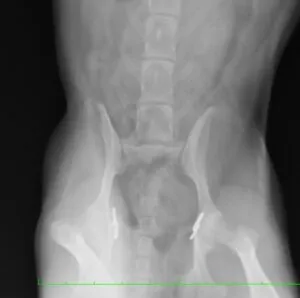

写真は両側の股関節脱臼をして整形外科の専門病院にて外科的整復を行った別症例。